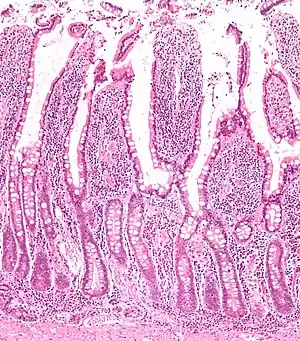

Microanatomy

The three sections of the small intestine look similar to each other at a microscopic level, but there are some important differences. The parts of the intestine are as follows:

| Layer | Duodenum | Jejunum | Ileum |

|---|---|---|---|

| Serosa | 1st part serosa, 2nd–4th adventitia | Normal | Normal |

| Muscularis externa | Longitudinal and circular layers, with Auerbach's (myenteric) plexus in between | Same as duodenum | Same as duodenum |

| Submucosa | Brunner's glands and Meissner's (submucosal) plexus | No BG | No BG |

| Mucosa: muscularis mucosae | Normal | Normal | Normal |

| Mucosa: lamina propria | No PP | No PP | Peyer's patches |

| Mucosa: intestinal epithelium | Simple columnar. Contains goblet cells, Paneth cells | Similar to duodenum, but the intestinal villus is long | Similar to duodenum, but the intestinal villus is short |

Digested food is now able to pass into the blood vessels in the wall of the intestine through either diffusion or active transport. The small intestine is the site where most of the nutrients from ingested food are absorbed. The inner wall, or mucosa, of the small intestine, is lined with intestinal epithelium, a simple columnar epithelium. Structurally, the mucosa is covered in wrinkles or flaps called circular folds, which are considered permanent features in the mucosa. They are distinct from rugae which are considered non-permanent or temporary allowing for distention and contraction. From the circular folds project microscopic finger-like pieces of tissue called villi (Latin for "shaggy hair"). The individual epithelial cells also have finger-like projections known as microvilli. The functions of the circular folds, the villi, and the microvilli are to increase the amount of surface area available for the absorption of nutrients, and to limit the loss of said nutrients to intestinal fauna.